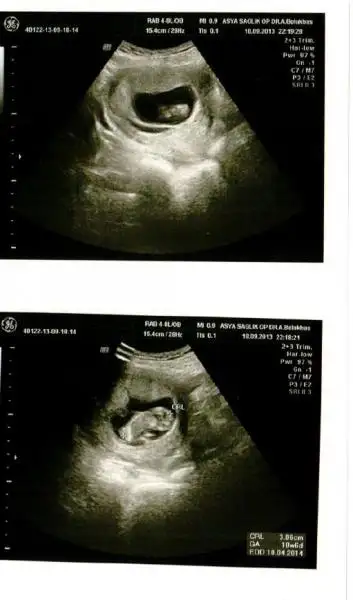

Eki Görüntüle 807467 ust kısımında kesenın dıbınde kanama alanı gozukuyor doktor hersey olabılır kan kuruyup yapısabılır dedı

Canım bak bende ekliyorum kanama alanını. Bizimki ilişki sonrası olmuştu. Doktor 2-3 gün güzelce dinlen geçer demişti ama kanamam tam 3 gün aralıklarla sürdü. Bi ara ped bile kullandımm. Korkma.

Bebişkomun şimdiki halini de ekliyorum rahatla :54::54:

Hayır canım alt tarata bi koyuluk var çizgi halinde. Kesenin etrafında vardı hep öyle çizgi çizgi. Geçti sonradan çok şükür. İnternette yazılanları okuyup okuyup telaşlanmıştım sen yapma. Yat dinlen.